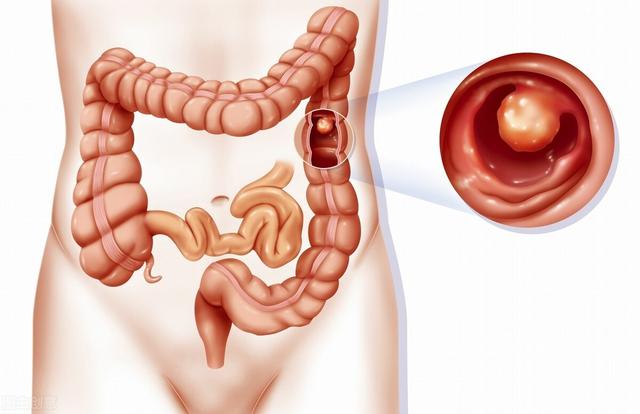

6.腸ポリープ

腸ポリープはがん化する可能性もあり、ポリープが複数ある場合は、早期の大腸がんを避けるため、定期的なフォローアップの大腸内視鏡検査と定期的な生検を受けるよう促す必要があるかもしれない。

腸の腺腫様ポリープ → 腸がん

腸ポリープは、腺腫性ポリープ、炎症性ポリープ、過形成性ポリープに分類される。腺腫性ポリープは5~15年でがんになる可能性がある。炎症性ポリープと過形成性ポリープは、現在のところ癌化する可能性は低いと考えられているが、大腸内視鏡下ではポリープの性状を形態学的に判断することができないため、一般的には大腸内視鏡下で切除し、病理標本にすることが推奨されている。最終的な判定が腺腫性ポリープであったとしても、また嵐の中で "リーキーフィッシュ "を起こさないように、毎年検査を受ける必要がある。

腸ポリープ

最も有望なミニオンは以下の通り。結腸・直腸ポリープ癌にエスカレートする可能性が最も高く、多くの場合、複数の分布があり、通常は隠れた増殖で、「変形」が結腸癌になることもある。

腸ポリープは表面が非常にもろく、また出血しやすい。 患者は血便に気づいたら受診するが、患者の状態ももはや深刻ではないことが多い。

腸ポリープには大きく分けて炎症性と腺腫性の2種類があり、前者はほとんどが悪性ではなく、後者は悪性の可能性が高い。

統計上、大腸がんの80~95%は腸ポリープから段階的に進行し、その過程には5~10年かかる!

ポリープから癌への進行性進展

健康な人は50歳から大腸内視鏡検査を受け、結果が正常であれば5年後に再検査することが推奨されています。ですから、症状が出るまで待たずに、私のことを思い出してください!

5.腸管ポリープ:家族性多発性腸管ポリープ症は染色体優性疾患であり、一つの遺伝子が多面的に発現する。大腸ポリープは腺腫性ポリープであり、発癌率は50%である。病気の経過の延長、加齢、免疫力の低下により発癌率はさらに高くなり、家族歴があれば男女ともに罹患する可能性がある。家族歴があると男女ともに大腸腺腫性ポリープが発生し、次の世代の年齢が進み、20歳前に大腸腺腫性ポリープがんが発生することさえある。また、一般的な腸管ポリープでも発癌のリスクはあり、腸管腫瘍の大部分は腸管腺腫から緩徐に発生する。 ポリープが大きいほど発癌率は高く、ポリープの数が多いほど発癌率は高く、ポリープの病理学的タイプでは腺腫性絨毛成分が多いほど発癌率は高く、先端部のある腺腫性ポリープは発癌率が低く、基部の広い腺腫性ポリープは発癌率が高く、直腸ポリープは発癌率が高い。

- 腸癌の前癌病変としての大腸多発性腺腫性ポリープ.大腸で増殖するため発見が容易ではなく、血便、粘液便、腸重積を呈することがあり、主に大腸内視鏡検査で発見される。定期的なフォローアップ大腸内視鏡検査で腸癌への進行を防ぐ。